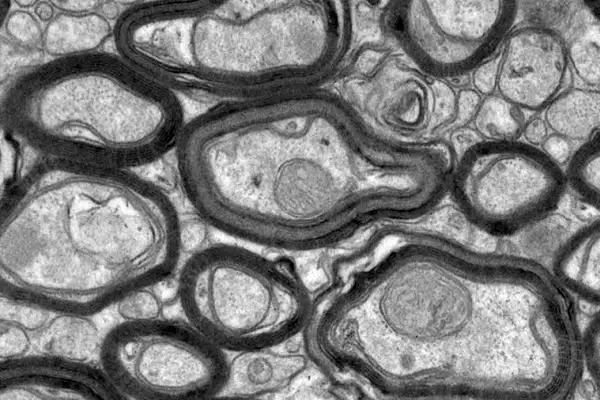

به گزارش نیواطلس، بیماری ام اس یکی از بیماری های خطرناکی است که در نتیجه حمله اشتباه سیستم ایمنی بدن به میلین ها رخ می دهد. میلین ها غلاف هایی هستند که وظیفه حفاظت از نورون های حافظ سیستم عصبی را بر عهده دارند.

محققان دانشگاه ملبورن برای غلبه بر این مشکل پپتیدهای مصنوعی (نوعی پلیمر کوچک) تولید کرده اند که قادر به بازتولید میلین های آسیب دیده است و می تواند پیشرفت بیماری ام اس را کند کند.

استفاده از این روش بر روی موش ها با موفقیت انجام شده و منجر به تولید و جایگزینی میلین ها شده است و پژوهشگران امیدوارند بتوانند در آینده روش مذکور را بر روی انسان ها هم با موفقیت آزمایش کنند.